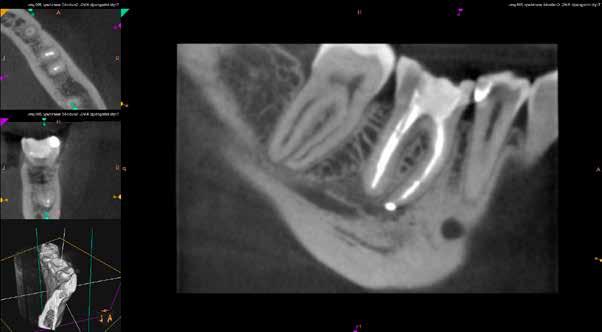

Mind a periapicalis röntgenfelvétel, mind a CBCT-felvétel igazolta, hogy a fragmentum mélyen a gyökércsatorna görbülete mögött, az apikális harmadban helyezkedik el a mesiobuccalis csatornában, valahol a mesiolingualis csatornával történő egyesülés után. Ezenfelül mind a mesialis, mind a distalis gyökércsúcs körül periapicalis gyulladás jelei voltak megfigyelhetőek (1–3. ábra). A betört eszköz nagyjából 5 mm-es hosszúsággal rendelkezett. A mesiolingualis csatornán keresztül a betört fragmentum mellett történő további gyökércsatorna-megmunkálást kockázatosnak ítéltük, mivel nagy esélyt láttunk rá, hogy így a másik eszköz is eltörik, amely pedig a gyökértömés elkészítését nehezítette volna. Azonban a SWEEPS technológiának és a biokerámia sealereknek köszönhetően más megoldási lehetőségek is nyitva álltak előttünk.

ábra: Kiindulási röntgen. A felvételen jól látható a betört eszköz és a periapikális lézió.

2. ábra: Kiindulási CBCT-felvétel. A betört eszköz mélyen a gyökércsatorna görbülete mögött található.

3. ábra: A betört eszköz vége jóval a mesiobuccalis és mesiolinguális csatorna egyesülésének pontja alatt helyezkedik el.